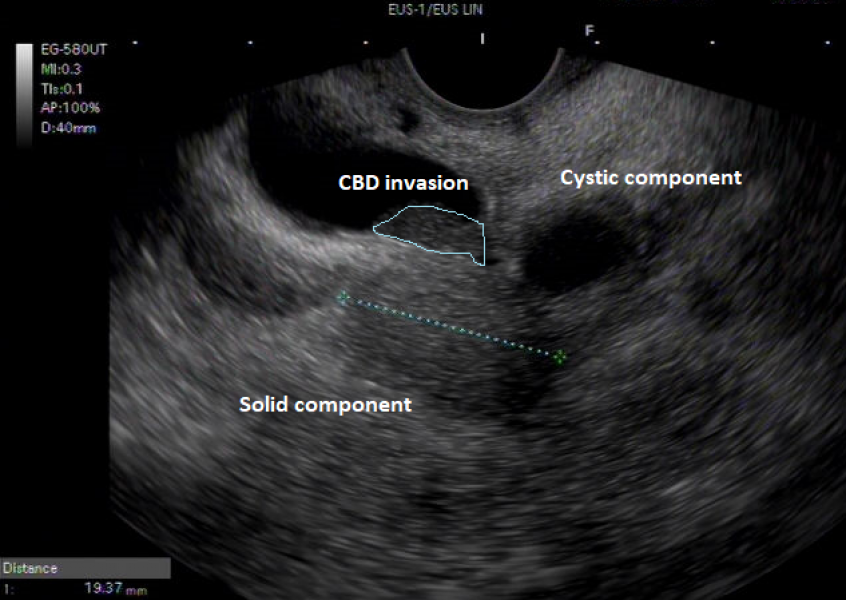

From IPMN to IPMN-derived invasive adenocarcinoma